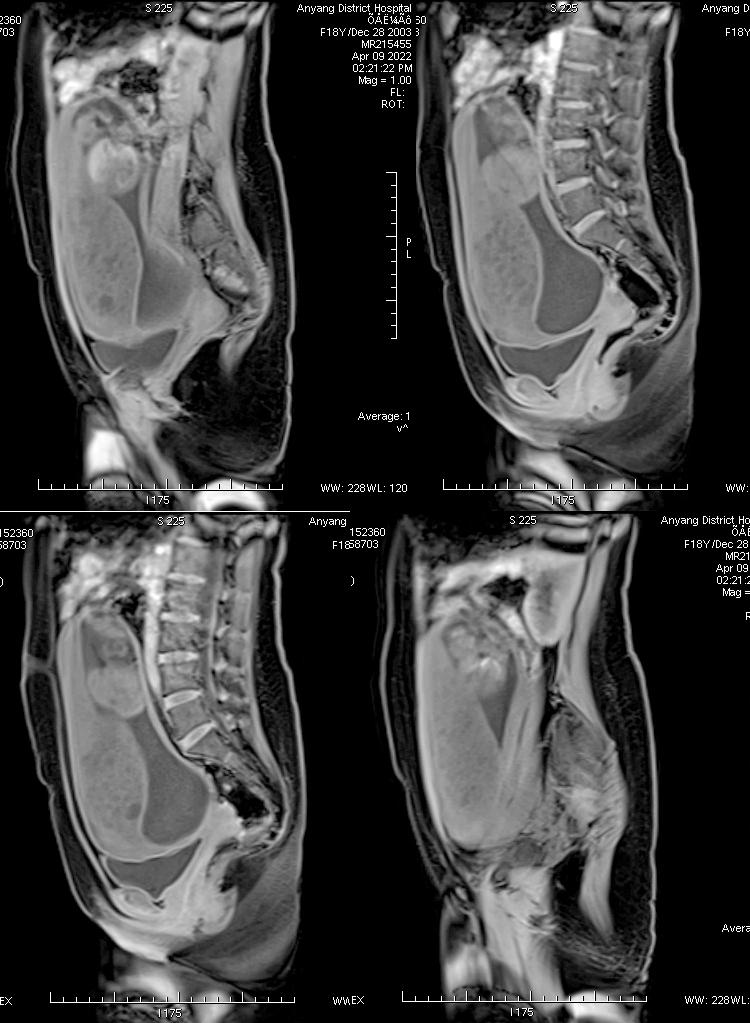

病例一

女,18 岁,孕 19 周 6 天,妊娠合并胎盘部分性葡萄胎 1 月余,病灶与子宫肌层分界清晰。

孕早 期因胃痛曾应用氨苄西林粉、西咪替丁、维生素 B6、山莨菪碱、胃炎颗粒、胃灵颗粒、吗丁啉对症治 疗。 外院彩超提示: 宫内妊娠,单活胎,胎儿室间隔缺损,胎盘 下方见异常不均质回声,范围约 109*41*108 mm,内呈蜂窝状改变,与胎盘分界不清,考虑部分性葡萄胎可能,建议终止妊娠。 为进一步终止妊娠就诊我院。